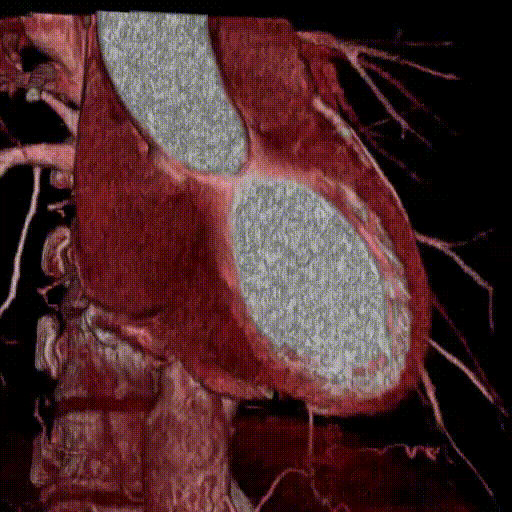

CT検査は通常からだを輪切りにしたような断面の画像を撮影しますが、各診療科の要望に応じて、様々な角度の断面(MPR画像といいます)を作成する場合があります。また、CT室・MRI室で撮影された画像をもとに専用の装置(ワークステーション)を用いて血管や臓器・病変部を見やすく加工したVR画像(いわゆる3D画像)や病気を解析するための画像を作成する場合があります。

図の心臓の画像はPhyziodynamicsという次世代の画像処理・加工を行うためのソフトで作成したものです。従来よりもはるかに滑らかな動きで心臓を観察できる画像を作成することができるようになりました。私たちは心臓以外にもこのソフトを生かした画像を作成できるよう日々模索しております。